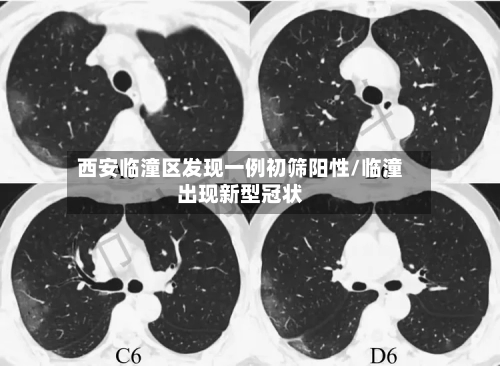

• 西安临潼区发现一例初筛阳性/临潼出现新型冠状